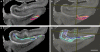

Ex vivo magnetic resonance imaging yields high resolution images that reveal detailed cerebral anatomy and explicit cytoarchitecture in the cerebral cortex, subcortical structures, and white matter in the human brain. Our data illustrate neuroanatomical correlates of limbic circuitry with high resolution images at high field. In this report, we have studied ex vivo medial temporal lobe samples in high resolution structural MRI and high resolution diffusion MRI. Structural and diffusion MRIs were registered to each other and to histological sections stained for myelin for validation of the perforant pathway. We demonstrate probability maps and fiber tracking from diffusion tensor data that allows the direct visualization of the perforant pathway. Although it is not possible to validate the DTI data with invasive measures, results described here provide an additional line of evidence of the perforant pathway trajectory in the human brain and that the perforant pathway may cross the hippocampal sulcus.